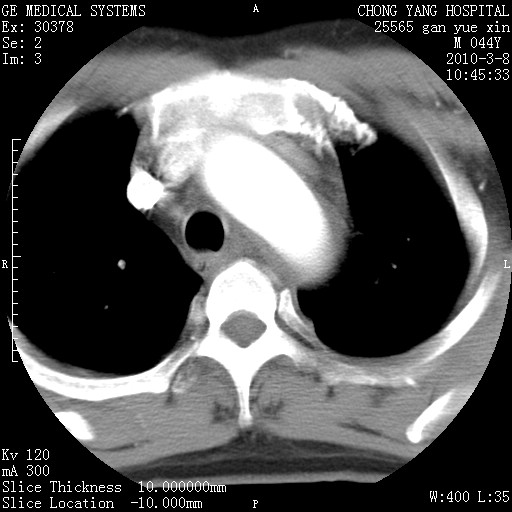

标题: CT24940:主动脉增强,典型病例。 [打印本页]

标题: CT24940:主动脉增强,典型病例。

夹层动脉瘤。

动脉夹层

夹层动脉瘤,典型

主动脉夹层。

动脉夹层的分型:

⒈debakey分型:根据主动脉夹层累及部位,分为三型:ⅰ型:原发破口位于升主动脉或主动脉弓部,夹层累及升主动脉、主动脉弓部、胸主动脉、腹主动脉大部或全部,少数可累及髂动脉。ⅱ型:原发破口位于升主动脉,夹层累及升主动脉,少数可累及部分主动脉弓。ⅲ型:原发破口位于左锁骨下动脉开口远端,根据夹层累及范围又分为ⅲa,ⅲb。ⅲa型:夹层累及胸主动脉。ⅲb型:夹层累及升主动脉、腹主动脉大部或全部。少数可累及髂动脉。

⒉stanford分型:a型:夹层累及升主动脉,无论远端范围如何。b型:夹层累及左锁骨下动脉开口以远的降主动脉。

夹层动脉瘤,少量胸水

夹层动脉瘤;左侧少量胸腔积液。

典型主动脉夹层。